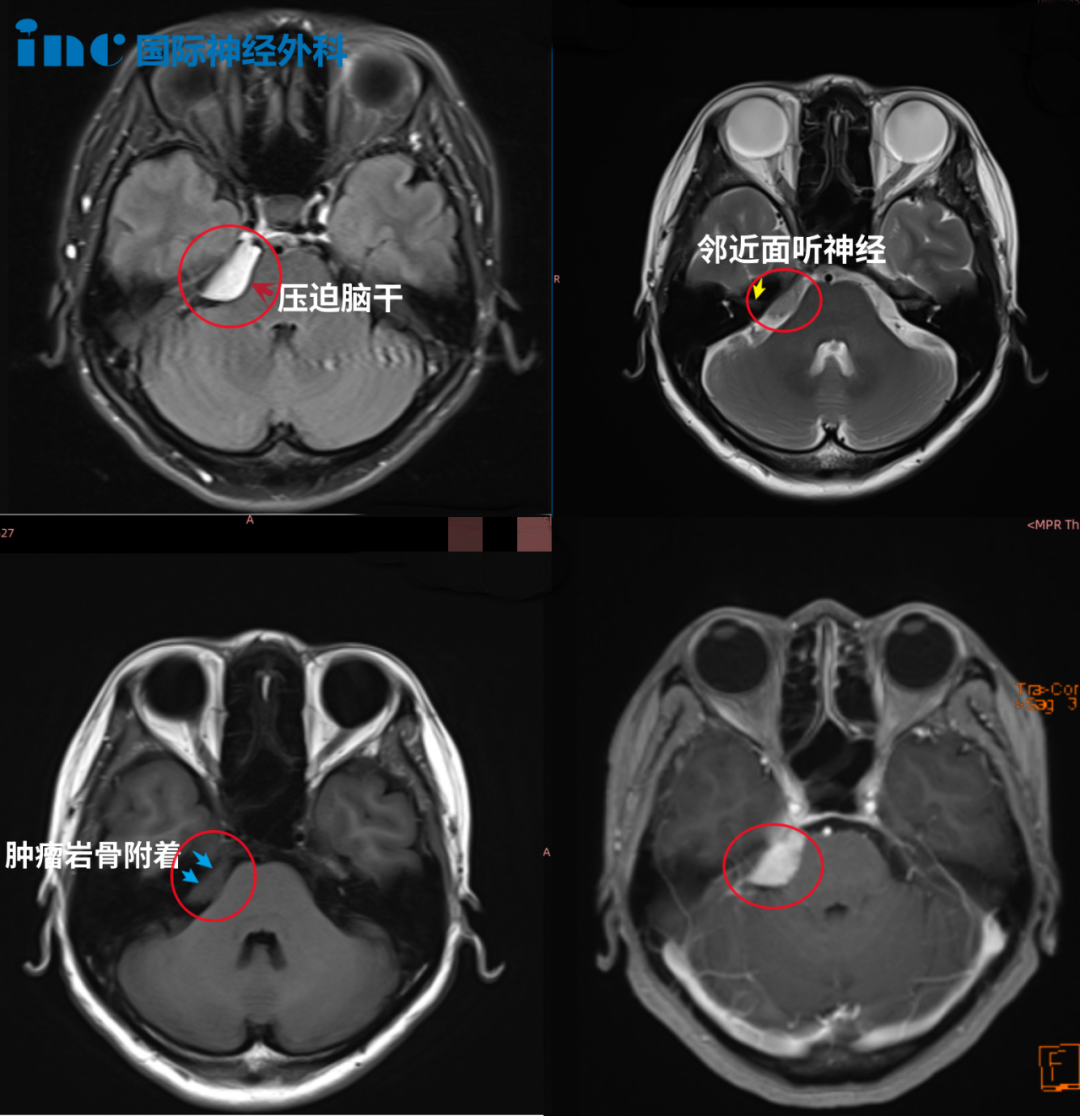

医生告知,右侧桥小脑角(CPA)区占位,肿瘤位置与三叉神经、面听神经、滑车神经等重要颅神经及海绵窦、小脑关系密切,已经压迫到脑干,手术治疗伤及神经的风险很大,也就是说如果手术做不好,可能面瘫、听力丧失、肢体瘫痪,甚至昏迷等。

苦苦的查询之中,他们找到INC巴教授。钟女士在INC的协助下与巴教授展开了咨询,巴教授在详细诊断病情后表示,肿瘤是典型的天幕脑膜瘤(Tentorial meningioma,位于桥小脑角区,是长在大脑与小脑之间硬脑膜隔上的脑膜瘤),侵犯到右侧Meckel腔,瘤体不是很大。如果是初治时,根据肿瘤的位置,大小和患者的年龄等因素,他会建议患者手术。

钟女士2022年1月影像检查结果显示:右侧桥小脑角区占位,肿瘤侵犯到右侧Meckel腔